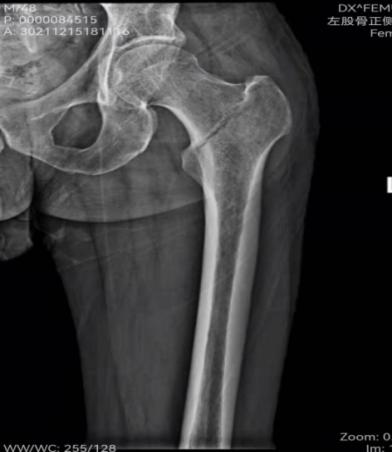

患者,48岁,有脑梗死后遗症且左侧肢体偏瘫,在家走路时不慎摔倒致左髋关节疼痛、活动受限入院。入院后查左侧髋关节X线片示:左股骨粗隆间骨折。骨外一科医疗团队在孙波主任主持下行病例讨论,并制定手术方案,决定行左股骨粗隆间骨折闭合复位内固定术(PFBN)。